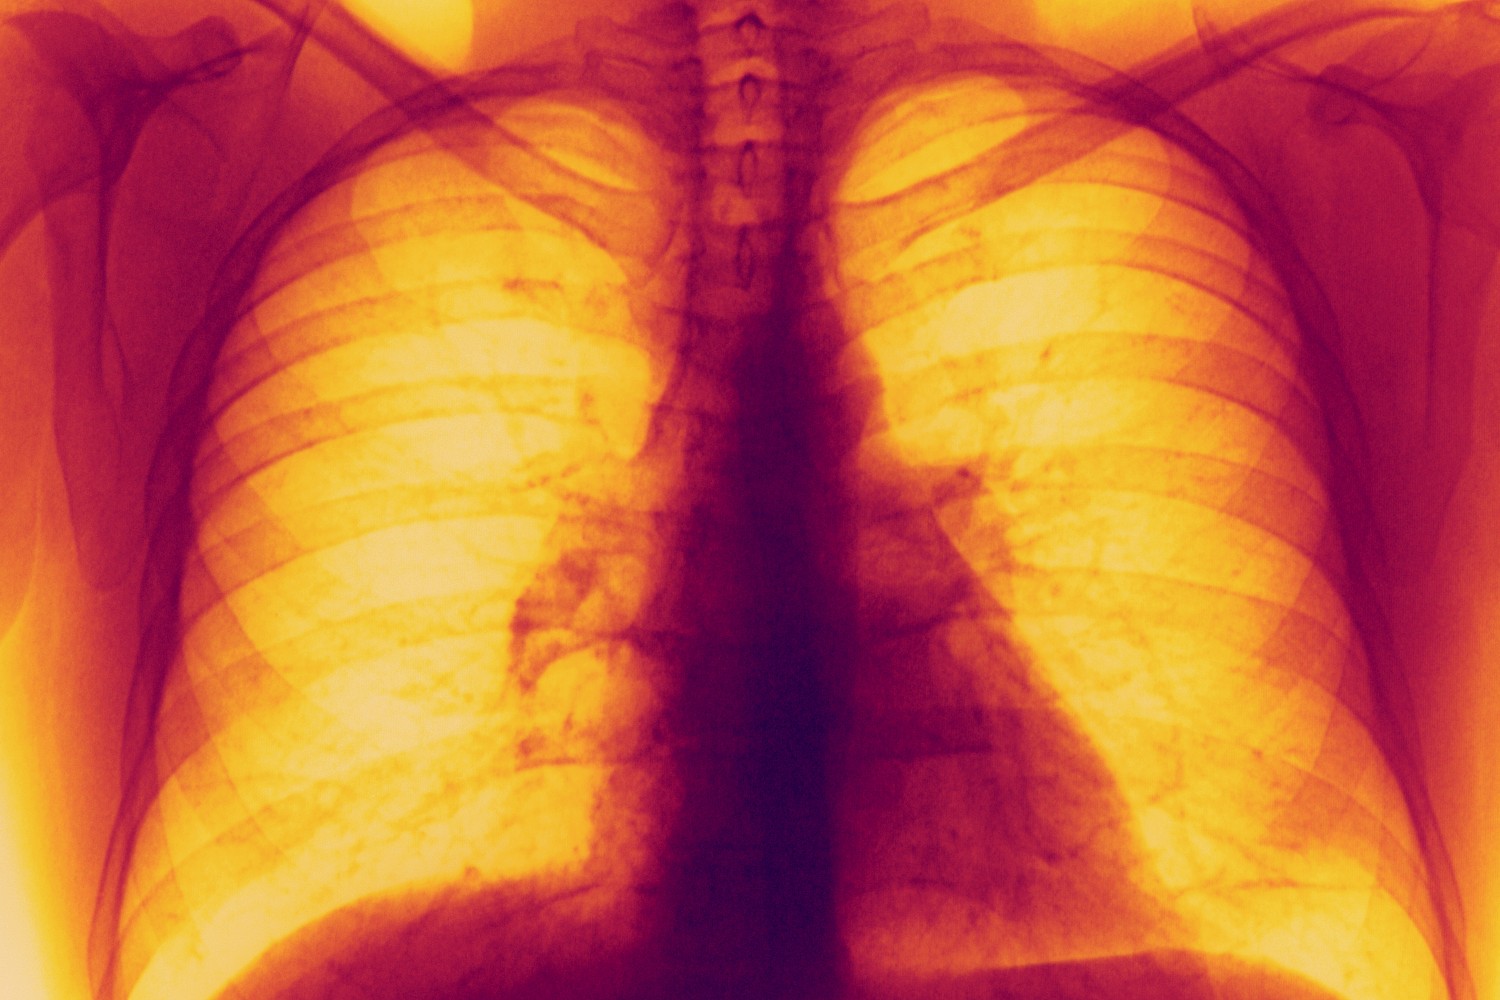

Lung X-rays

A new medication could be a game changer for lung cancer treatment.

Getty Images